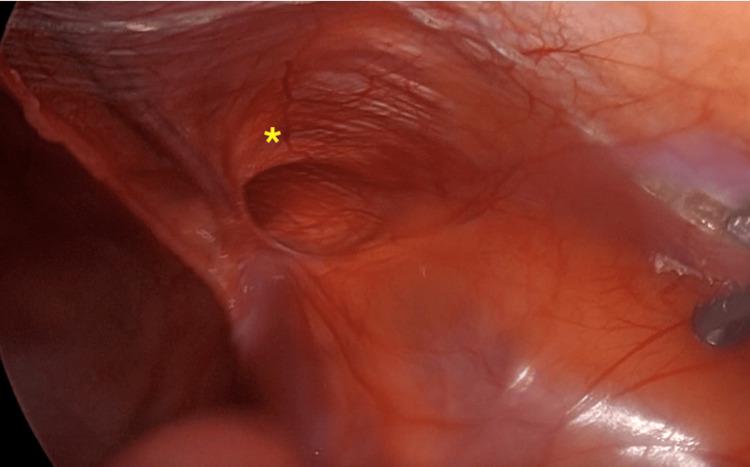

Inguinal hernia repair is one of the most common surgical procedures. Traditionally, traumatic fixations have been used to prevent mesh migration, resulting in chronic pain in the groin. However, a non-traumatic alternative with cyanoacrylate glue is offered. A 50-year-old male patient underwent elective surgery for inguinal hernia repair. During the surgery, it was decided to use cyanoacrylate glue for mesh fixation without complications. In his follow-up consultation, the patient showed a satisfactory course. The use of cyanoacrylate glue, a synthetic resorbable adhesive, for more rapid wound closure has shown favorable results. It is characterized by a low rate of complications and a significant decrease in groin pain in the short- and medium-term. This technique is considered a viable and effective alternative for the reduction of complications, with promising clinical results.